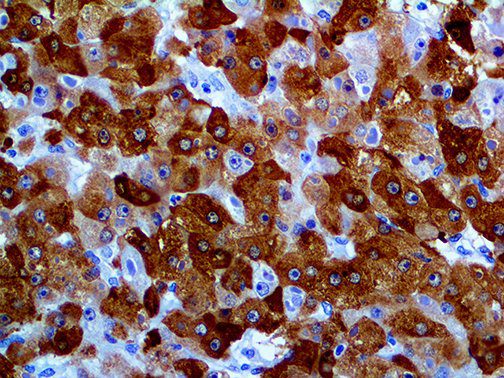

The first cytokines released are interleukin 1β (IL-1β) and tumor necrosis factor-α (TNF-α), which attract a variety of circulating white blood cells (WBCs) to the infection site, including neutrophils, monocytes, macrophages, and natural killer (NK) cells. This response, along with the antipathogenic chemicals released by these cells (i.e., complement), comprise the innate immune response. These cells directly attack the invading pathogen and also release additional cytokines, chief among them interleukin-1 and 6 (IL-6). IL-6 is essential for invoking the adaptive immune response, which calls T-cells, B-cells, and T helper (Th) cells to the infection site. IL-6 also stimulates further recruitment, proliferation and activation of macrophages.

It is the ICU physician who is most likely to witness one of the deadliest manifestations of the abnormal immunological response, the cytokine storm syndrome (CSS). This response is also referred to by some as the cytokine release syndrome (CRS). CSS is characterized by continuous activation and expansion of macrophage and lymphocyte populations, which secrete large amounts of cytokines, causing the cytokine storm. This massive cytokine release is akin to hemophagocytic lymphohistiocytosis (HLH) disease, a syndrome characterized by initial unchecked and persistent activation of cytotoxic T lymphocytes and NK cells.

This activation induces inflammatory monocytes to highly express IL-6, starting a localized and then systemic cascade effect that results in hyperproduction of IL-6, which accelerates the inflammatory process. Because IL-6 also increases vascular permeability, excessive levels cause blood vessels to become very leaky. This, along with clotting factors released from vascular endothelial cells, stimulates the coagulation cascade, resulting in microthrombosis (tiny clots), which leads to ischemia and tissue death of the kidney, intestines, heart, liver, brain and extremities.